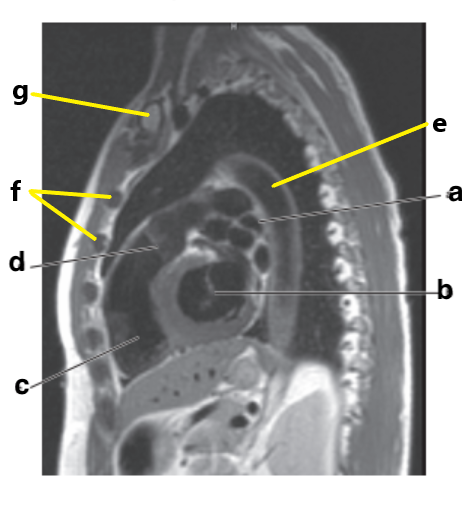

What is letter e ?

Aortic Arch

What is letter a ?

Left atrium

What is letter b ?

Bicuspid valve / LT AV valve

What is letter g ?

Descending thoracic aorta

Descending aorta

Identify the structure labeled with "e":

Liver

What is letter d ?

Thoracic vertebra

What is letter f ?

Sternum